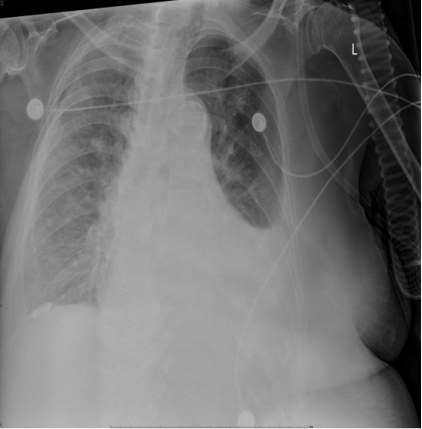

• 床旁胸片(图1):两肺纹理略多,稍乱模糊,两肺渗出,左肺渗出较2024年3月13日前片稍吸收,左侧胸腔积液较前片增多,右侧积液较前片吸收,纵隔增宽,心影增大。

图1  患者床旁胸片(2024-03-15)